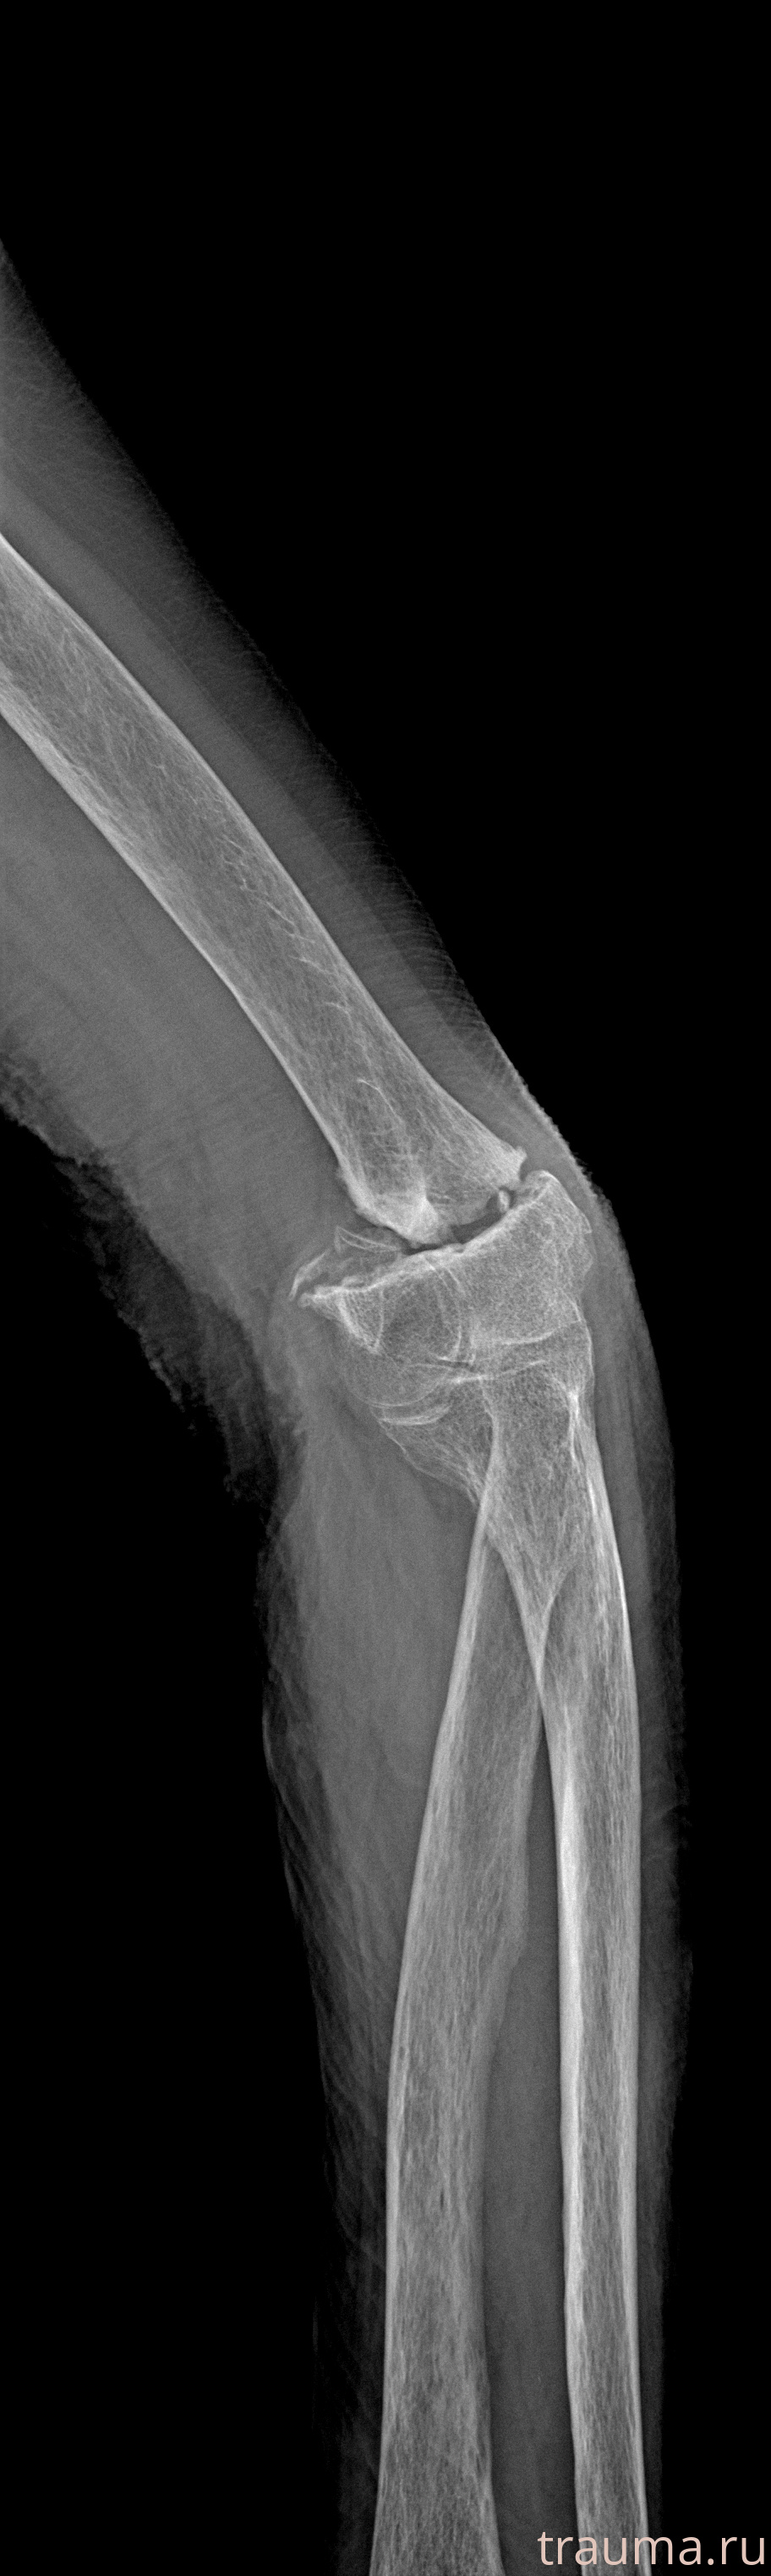

Рентгенограммы

Рентген на дому: по вашему адресу приезжает врач-рентгенолог, травматолог-ортопед с мобильным рентгеновским аппаратом, проводит диагностику травмы или заболевания, делает необходимые рентгенограммы, дает рекомендации по дальнейшему лечению. Получить качественные снимки в домашних условиях возможно благодаря уникальной методике, разработанной МосРентген Центром для института  Склифосовского